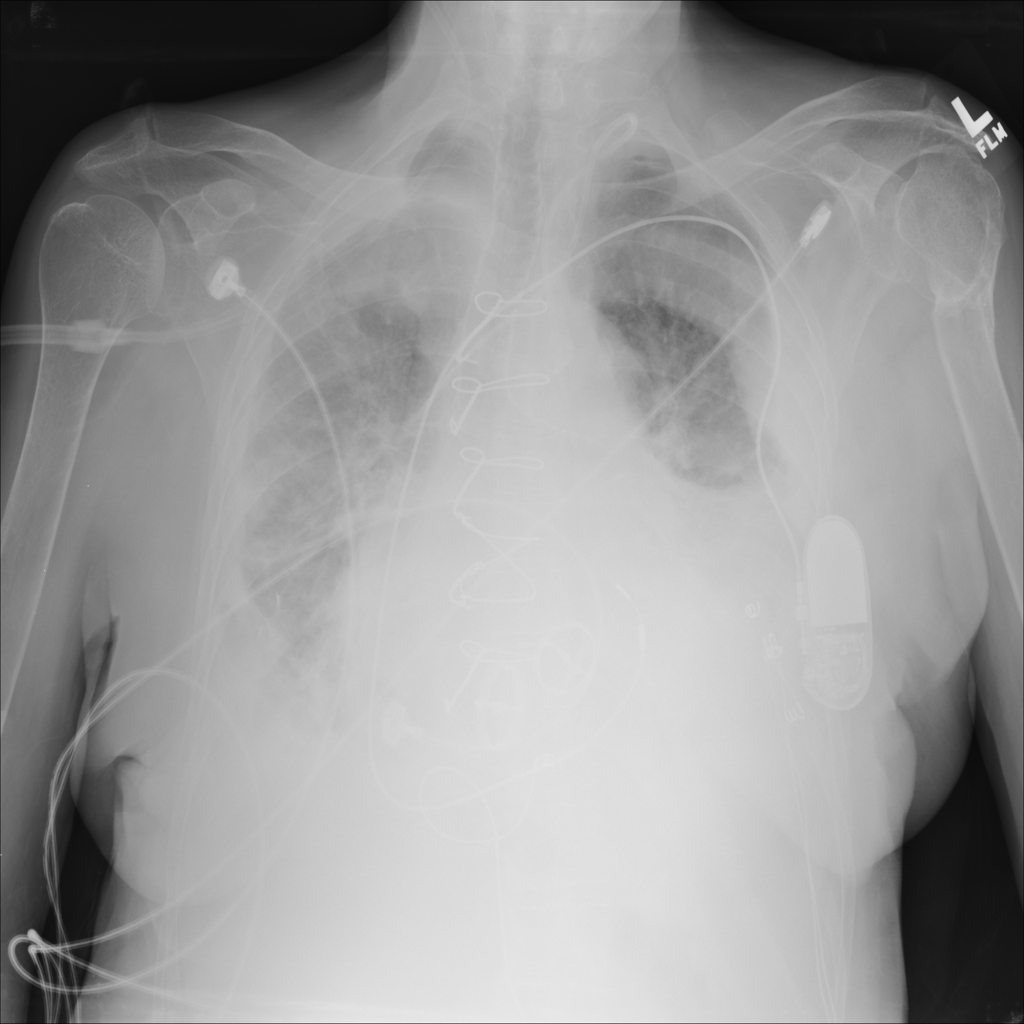

PAT-E81B · IMG-000Effusion

PAT-E81B · IMG-000

PA